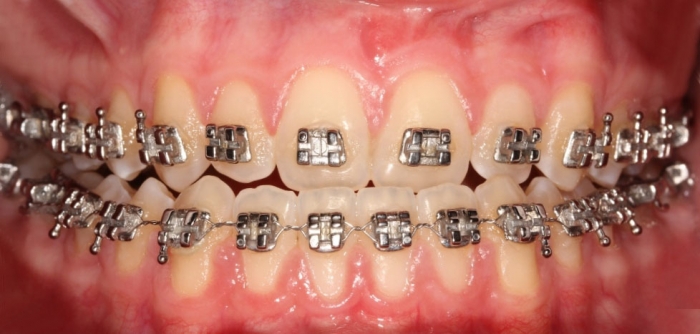

Mordida inicial - Clínica Cliniface

Mordida inicial